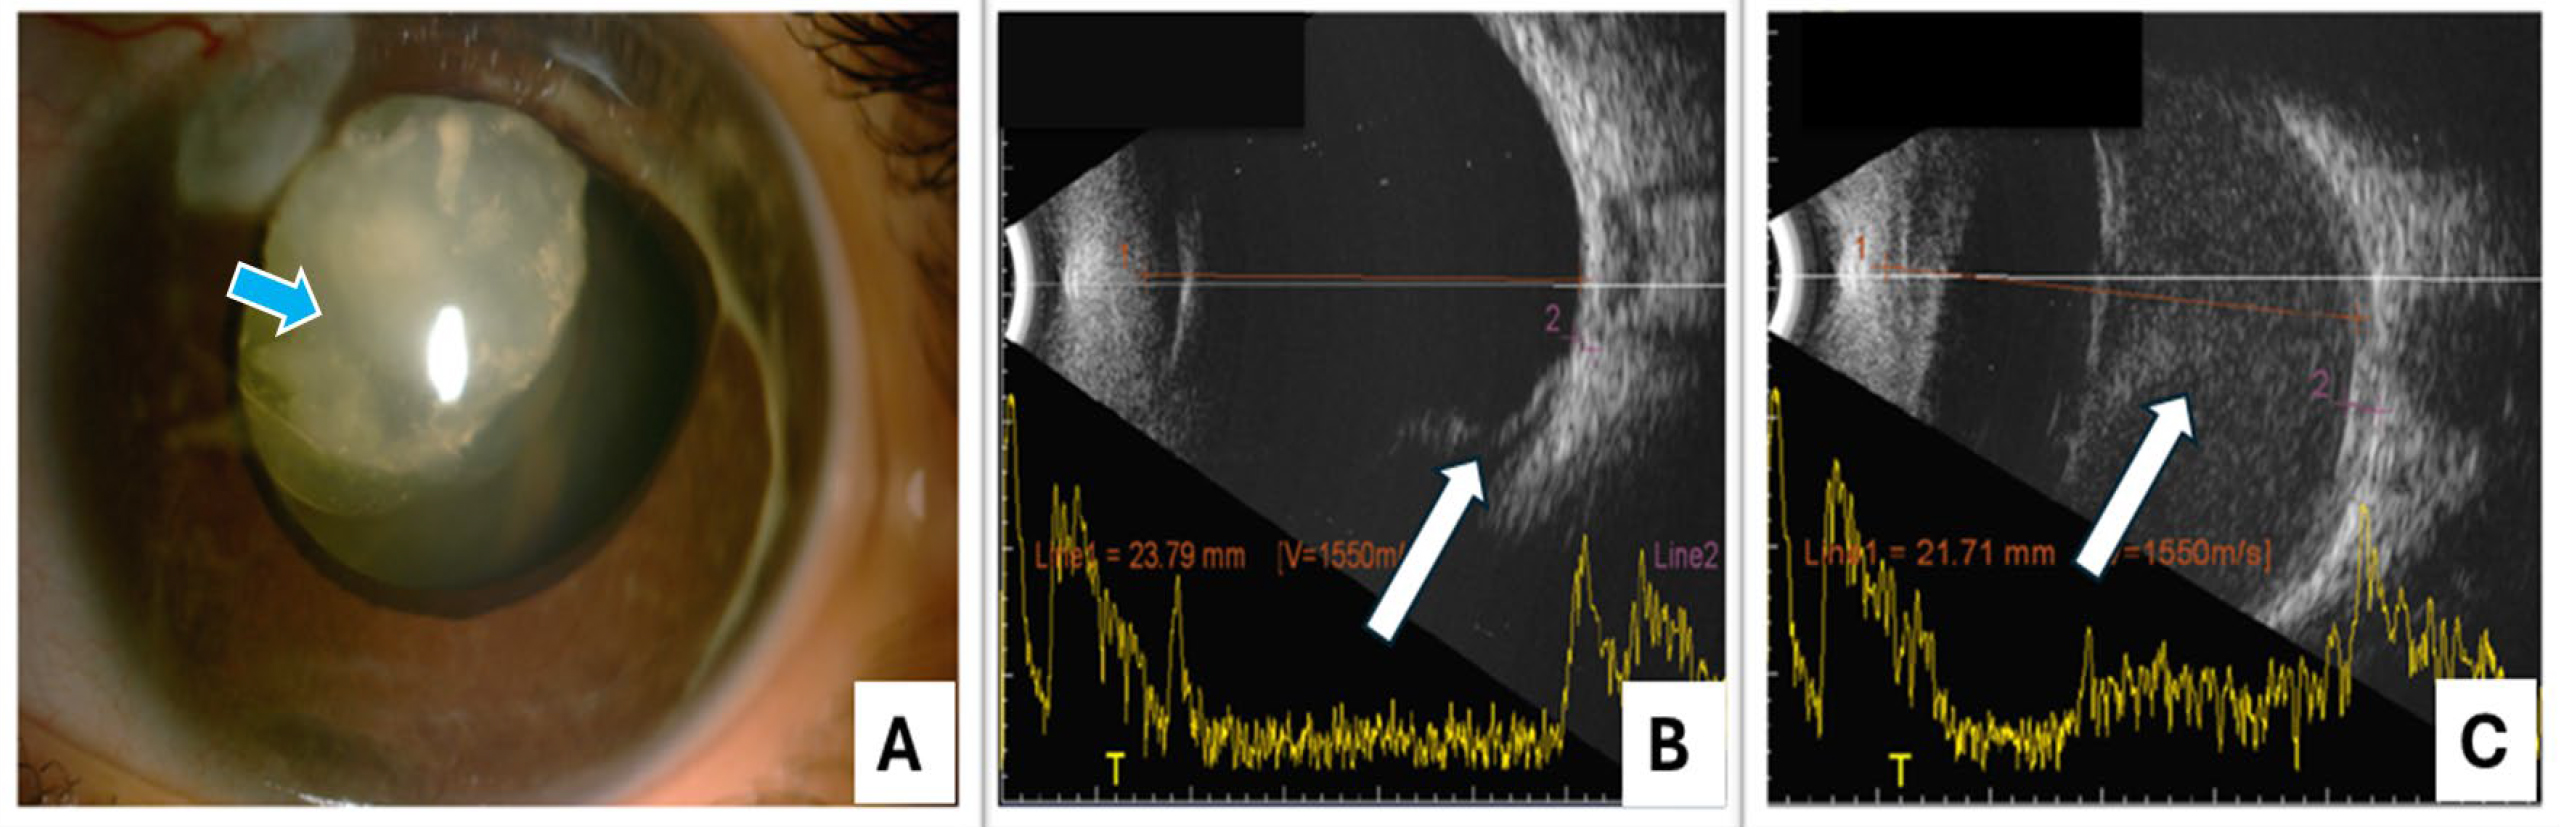

Figure 4. Ocular status of posterior segment complications in in patient associated with LTBP2 variation. A: Anterior segment photograph showing a hypotonus eye with subluxated microspherophakic cataractous lens (marked by arrow)

in an eye with retinal detachment in case P9. B: B-scan ultrasound showing retinal detachment (arrow marked) in an eye post lensectomy in case P8. C: Shows B -scan with suprachoroidal haemorrhage (arrow marked) following combined trabeculotomy with trabeculectomy done elsewhere

in case P9.